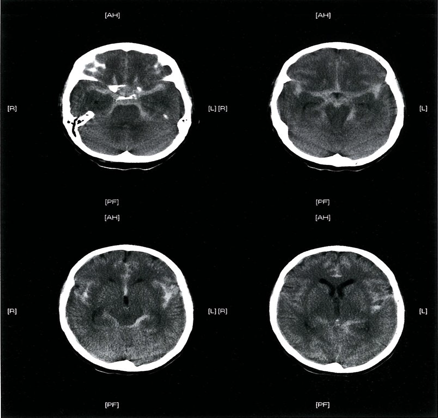

Subarachnoid hemorrhage - CT head (without contrast; axial plane)

Multiple areas of high attenuation in the basal cisterns, Sylvian fissures, and sulci are characteristic of extensive subarachnoid hemorrhage.

- Hyperdense CSF in the basal cisterns, sylvian fissure and subarachnoid space